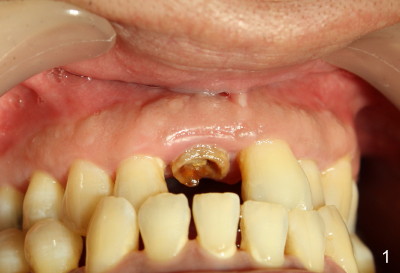

Quick Atrophy after Extraction

The upper right central incisor is nonsalvageable for 37-year-old man (Fig.1).  After atraumatic extraction, localized scaling is performed.  Collagen plug is inserted.  PGA suture is used to keep the plug in place.

Does this post-extraction infection happens often, but without being noticed?  Four quadrant scaling and root planing should have been conducted prior to extraction to reduce infection in this case. Note calculus in the lower anteriors (Fig.1).   Does immediate implant with bone graft prevent loss of the labial plate?   What should we do for this case now?  Wait for 2-3 months before implant placement?  Or bone graft after the infection is under control?